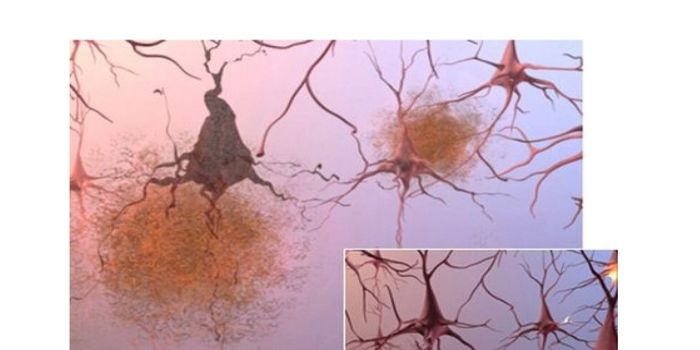

JUN 08, 2016NeuroscienceIt’s been known for a while that plaques of the protein amyloid beta are part of the pathology of Alzheimer’ ...

MAY 11, 2016ImmunologyThe brain’s immune system potentially could be harnessed to help clear amyloid plaques, which are a hallmark of Al ...

APR 05, 2016NeuroscienceAlzheimer’s Disease (AD) is the most common form of dementia, currently affecting 5.5 million people in the U.S. T ...

FEB 26, 2016NeuroscienceStudies with genetically modified mice have unveiled additional connections between the immune system and Alzheimer&rsqu ...

JAN 18, 2016NeuroscienceAlzheimer’s disease (AD) and other forms of dementia are on the rise. There is no known cause of AD and there isn& ...

OCT 12, 2015NeuroscienceAlzheimer’s disease and other forms of dementia are estimated to grow exponentially over the next five decades. In ...

SEP 27, 2015NeuroscienceAmyloids, fibrous protein clumps often associated with diseases such as Alzheimer’s disease, form characteristic p ...